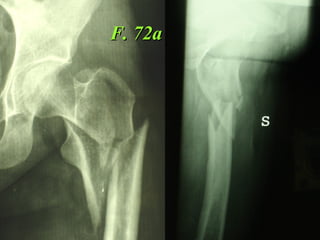

F. 72a

3  INSUCCESSI